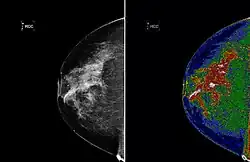

The left image shows an original mammogram before MED-SEG processing. The image on the right, with region of interest (white) labeled, shows a mammogram after MED-SEG processing.

Medical imaging standards such as DICOM provide general and application-specific mechanisms to support various use-cases.